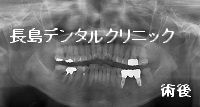

2、インプラント埋入

3本欠損のため

その両端に

2本インプラントを埋入し

残りの1歯を真ん中で支える

形状のブリッジを製作する

予定です。

3、被せ物の装着

インプラントを埋入3か月後に

骨との結合(オッセオインテグレーション)を

確認出来たら

うリッジの製作に移ります。